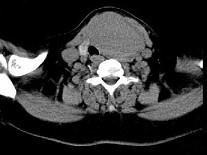

问题 女,56岁,发现颈部肿块1月余,CT如图所示,最可能诊断为()

选项 A.甲状舌管囊肿 B.甲状腺乳头状癌 C.甲状腺原发淋巴瘤 D.甲状腺腺瘤 E.甲状腺脓肿

答案 D